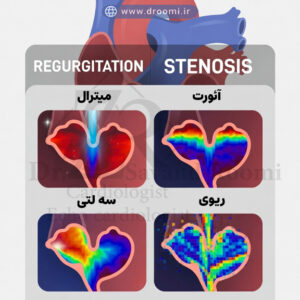

این تصویر بیماریهای دریچهای قلب را به دو گروه نارسایی و تنگی همراه با مثالهای داپلر رنگی نمایش میدهد.

بیماریهای دریچه قلب از جمله اختلالات رایج قلبی-عروقی هستند که میتوانند کیفیت زندگی افراد را به طور قابل توجهی تحت تأثیر قرار دهند. این بیماریها عمدتاً به دو دسته اصلی تقسیم میشوند: نارسایی دریچه قلب (رگورژیتاسیون، که در آن دریچه به درستی بسته نمیشود و خون به عقب بازمیگردد) و تنگی دریچه (استنوز، که دریچه تنگ شده و جریان خون را محدود میکند). تشخیص زودهنگام این مشکلات با استفاده از اکوکاردیوگرافی داپلر دریچه قلب و تصاویر اکو داپلر رنگی دریچههای قلب امکانپذیر است و در مراکز پیشرفته مانند کلینیک دکتر سوندرومی در شیراز، با دقت بالا انجام میشود. در ادامه به بررسی انواع شایع این بیماریها میپردازیم.

نارسایی (رگورژیتاسیون) دریچه میترال و آئورت

رگورژیتاسیون (نارسایی) دریچه آئورت و میترال از شایعترین انواع نارسایی دریچهای هستند. در نارسایی دریچه میترال، خون از بطن چپ به دهلیز چپ بازمیگردد که میتواند ناشی از آسیب لتها، عفونت یا بیماریهای زمینهای باشد. این مشکل اغلب با اکو رنگی نارسایی دریچه میترال به وضوح قابل مشاهده است، جایی که جریان خون بازگشتی به صورت جت رنگی ظاهر میشود.

به طور مشابه، نارسایی دریچه آئورت باعث بازگشت خون از آئورت به بطن چپ میشود و فشار بر قلب را افزایش میدهد. اکو داپلر رنگی برای تنگی آئورت و نارسایی آن، ابزار کلیدی برای ارزیابی شدت مشکل است و به متخصصان کمک میکند تا درجه regurgitation را دقیق اندازهگیری کنند.

تنگی (استنوز) دریچه میترال و آئورت

تنگی دریچه میترال اغلب در اثر تب روماتیسمی ایجاد میشود و جریان خون از دهلیز چپ به بطن چپ را محدود میکند، که منجر به فشار بر ریهها میگردد. تنگی دریچه آئورت نیز، که معمولاً با افزایش سن یا بیماریهای مادرزادی مرتبط است، پمپاژ خون به بدن را دشوار میسازد. تشخیص تنگی دریچه قلب در شیراز با استفاده از اکو داپلر رنگی برای تنگی آئورت انجام میشود و سرعت جریان خون را به دقت نشان میدهد.

این تصاویر داپلر رنگی، تفاوت جریان خون در حالت طبیعی و تنگی را به وضوح نمایش میدهند و به بهترین متخصص اکوکاردیوگرافی دریچه قلب شیراز کمک میکنند تا درمان مناسب، از دارو تا جراحی، را پیشنهاد دهد.

بیماریهای دریچه تریکوسپید و ریوی

دریچههای سمت راست قلب، یعنی تریکوسپید و پولمونیک (ریوی)، کمتر دچار مشکل میشوند، اما نارسایی تریکوسپید اغلب ثانویه به فشار خون ریوی یا مشکلات بطن راست است. تنگی این دریچهها معمولاً مادرزادی است. تصاویر اکو داپلر رنگی دریچههای قلب جریان خون غیرعادی در این دریچهها را به خوبی نشان میدهد، مانند جت رنگی در نارسایی تریکوسپید.